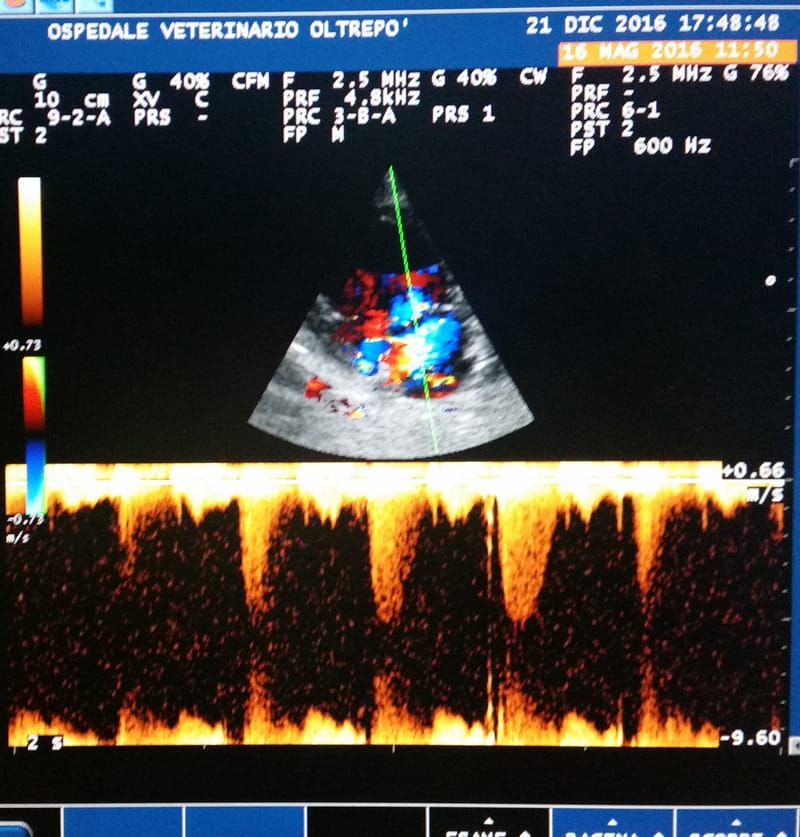

ECOCARDIOGRAFIA

Come per l'ecografia addominale permette, senza arrecare danno al paziente, di valutare l'anatomia e la funzionalità del cuore in tutte le sue strutture. Esame fondamentale in cardiologia.